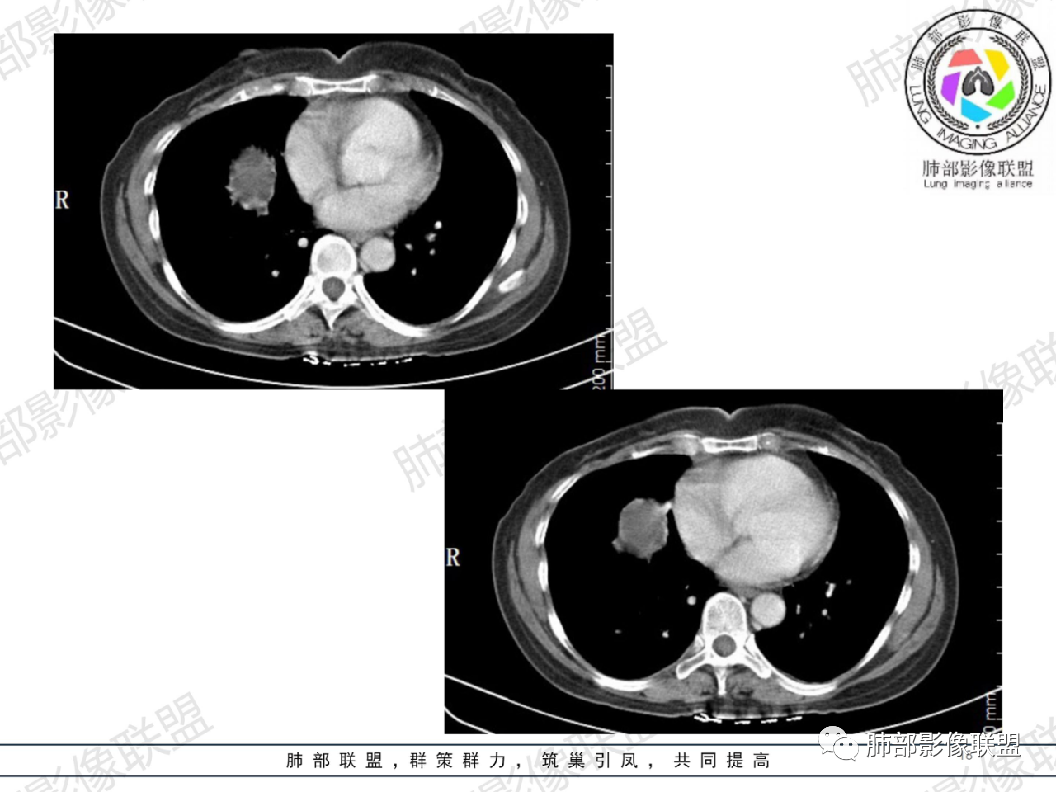

病例一结果:先天性囊性腺瘤样畸形

病例二结果:肺错构瘤样改变伴支气管扩张(支气管闭锁)

尘缘: 所以这个最终的病理诊断应该是包括两部分:既有支气管囊肿(影像所见),也有腺瘤样改变(这个只能病理可见,影像上显示不出来)。最终病理诊断综合为为囊腺瘤样畸形,没有任何问题,咱们大家影像诊断的支气管囊肿也没有任何问题。

其实不管是支气管囊肿,还是支气管闭锁,还是CCAM,他们都是来源于支气管先天发育异常的一大类病变,前两者之间有时候很不好区别,前两者与CCAM的区别主要是看是否有腺瘤样改变。尤其是单发大囊肿的CCAM,与支气管囊肿在影像上是根本区别不了的。只有在镜下看是否合并有腺瘤样改变来区分。

大雄: 病理镜下支气管扩张伴粘液样物质结合影像符合支气管闭锁

其次,支气管闭锁也是支气管先天异常的一种,错构瘤也是支气管发育异常(支气管错构)而支气管本身也有软骨成分,对于先天发育异常的支气管闭锁,局部发生支气管错构(软骨成分增加等也很正常,病理可能就根据这个报错构瘤样改变了)

实际上这就是一个支气管闭锁,同时伴有局部脉管增生和软骨成分而已。

可以认为是错构瘤的前身改变。错构瘤也有生长过程,先出现支气管错构,再慢慢生长成错构瘤。

如果病理结合影像,诊断应该是:支气管闭锁伴支气管错构畸形。这样更准确。